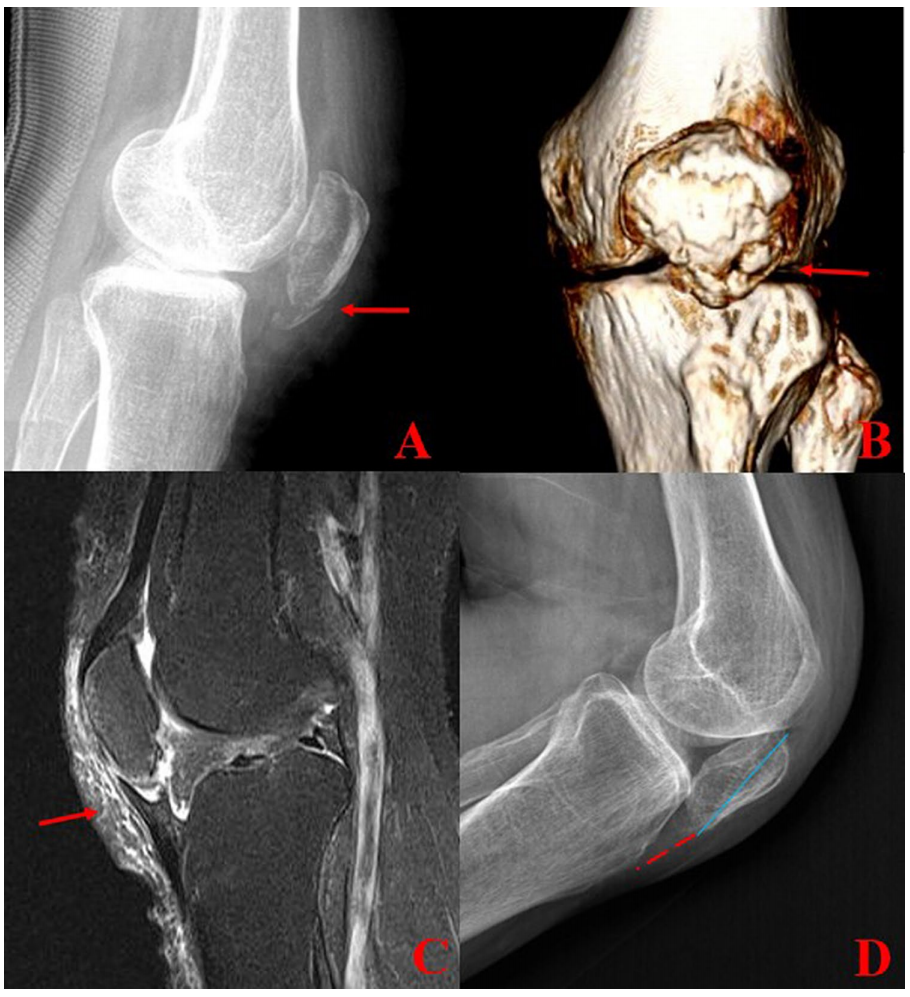

我们使用Insall–Salvati比值评估髌骨的上-下位置。与正常膝关节相比,患膝的Insall–Salvati比值平均为0.73,该小于0.8的比值意味着髌骨低位(表2)。特别是,在1例髌骨下极骨膜套袖撕脱骨折患者中(图6),缝线锚钉固定后4年随访时,Insall–Salvati比值为0.38(髌骨低位)。活动范围为0-130度。IKDC评分为71,Lysholm评分为85,KOOS评分为82。她对最终临床结果非常满意,仅偶尔有膝前疼痛。组内相关系数(ICC)及95%置信区间(CI)为0.980(0.951-0.992)( p<0.05)。评估者间可靠性的ICC及95% CI为0.972(0.940-0.988)( p<0.05)。

图6 一例髌骨骨膜套袖撕脱骨折患者。X线片和3D CT显示髌骨下极粉碎性骨折(a, b)。MRI清晰显示髌骨骨膜套袖撕脱骨折(箭头)。缝线锚钉固定后4年随访时Insall–Salvati比值为0.38(髌骨低位)(D)